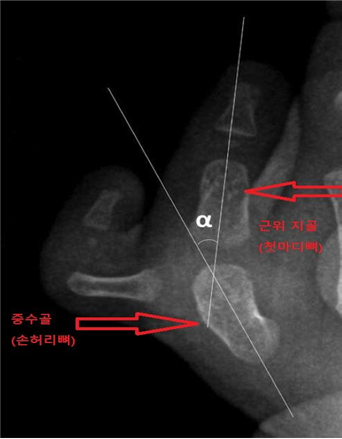

연구팀은 플랫 4형 엄지 다지증 환자 78명의 치료 결과를 추적·관찰했다. 이 중 절골술을 시행한 환자는 40명, 단순 연부 조직 재건술을 받은 환자는 38명이었다. 성별, 나이 등 인구통계학 정보는 물론, 수술 전·후 중수골-엄지손가락간 각도(MDA), 수술 후 손 기능 점수(JSSH 체계) 등을 수집해 분석했다.

연구팀은 절골술이 필요한 환자의 수술 전 중수골-엄지손가락간 각도(MDA) 기준점을 찾아냈다. 수술 이전 중수골-엄지손가락간 각도가 10.8° 이상인 경우, 절골술을 선택하는 것이 단순 연부조직 재건술보다 결과가 우수했다.

서울대병원 정형외과 김지형 교수는 “기존 다지증의 경우, 의사의 경험에 의존해 수술법을 결정하는 경우가 많았다”며 “이번 연구는 엄지 중수 수지 관절에서 10.8도 이상 각 변형이라는 객관적인 기준을 제시했다”고 의의를 밝혔다.